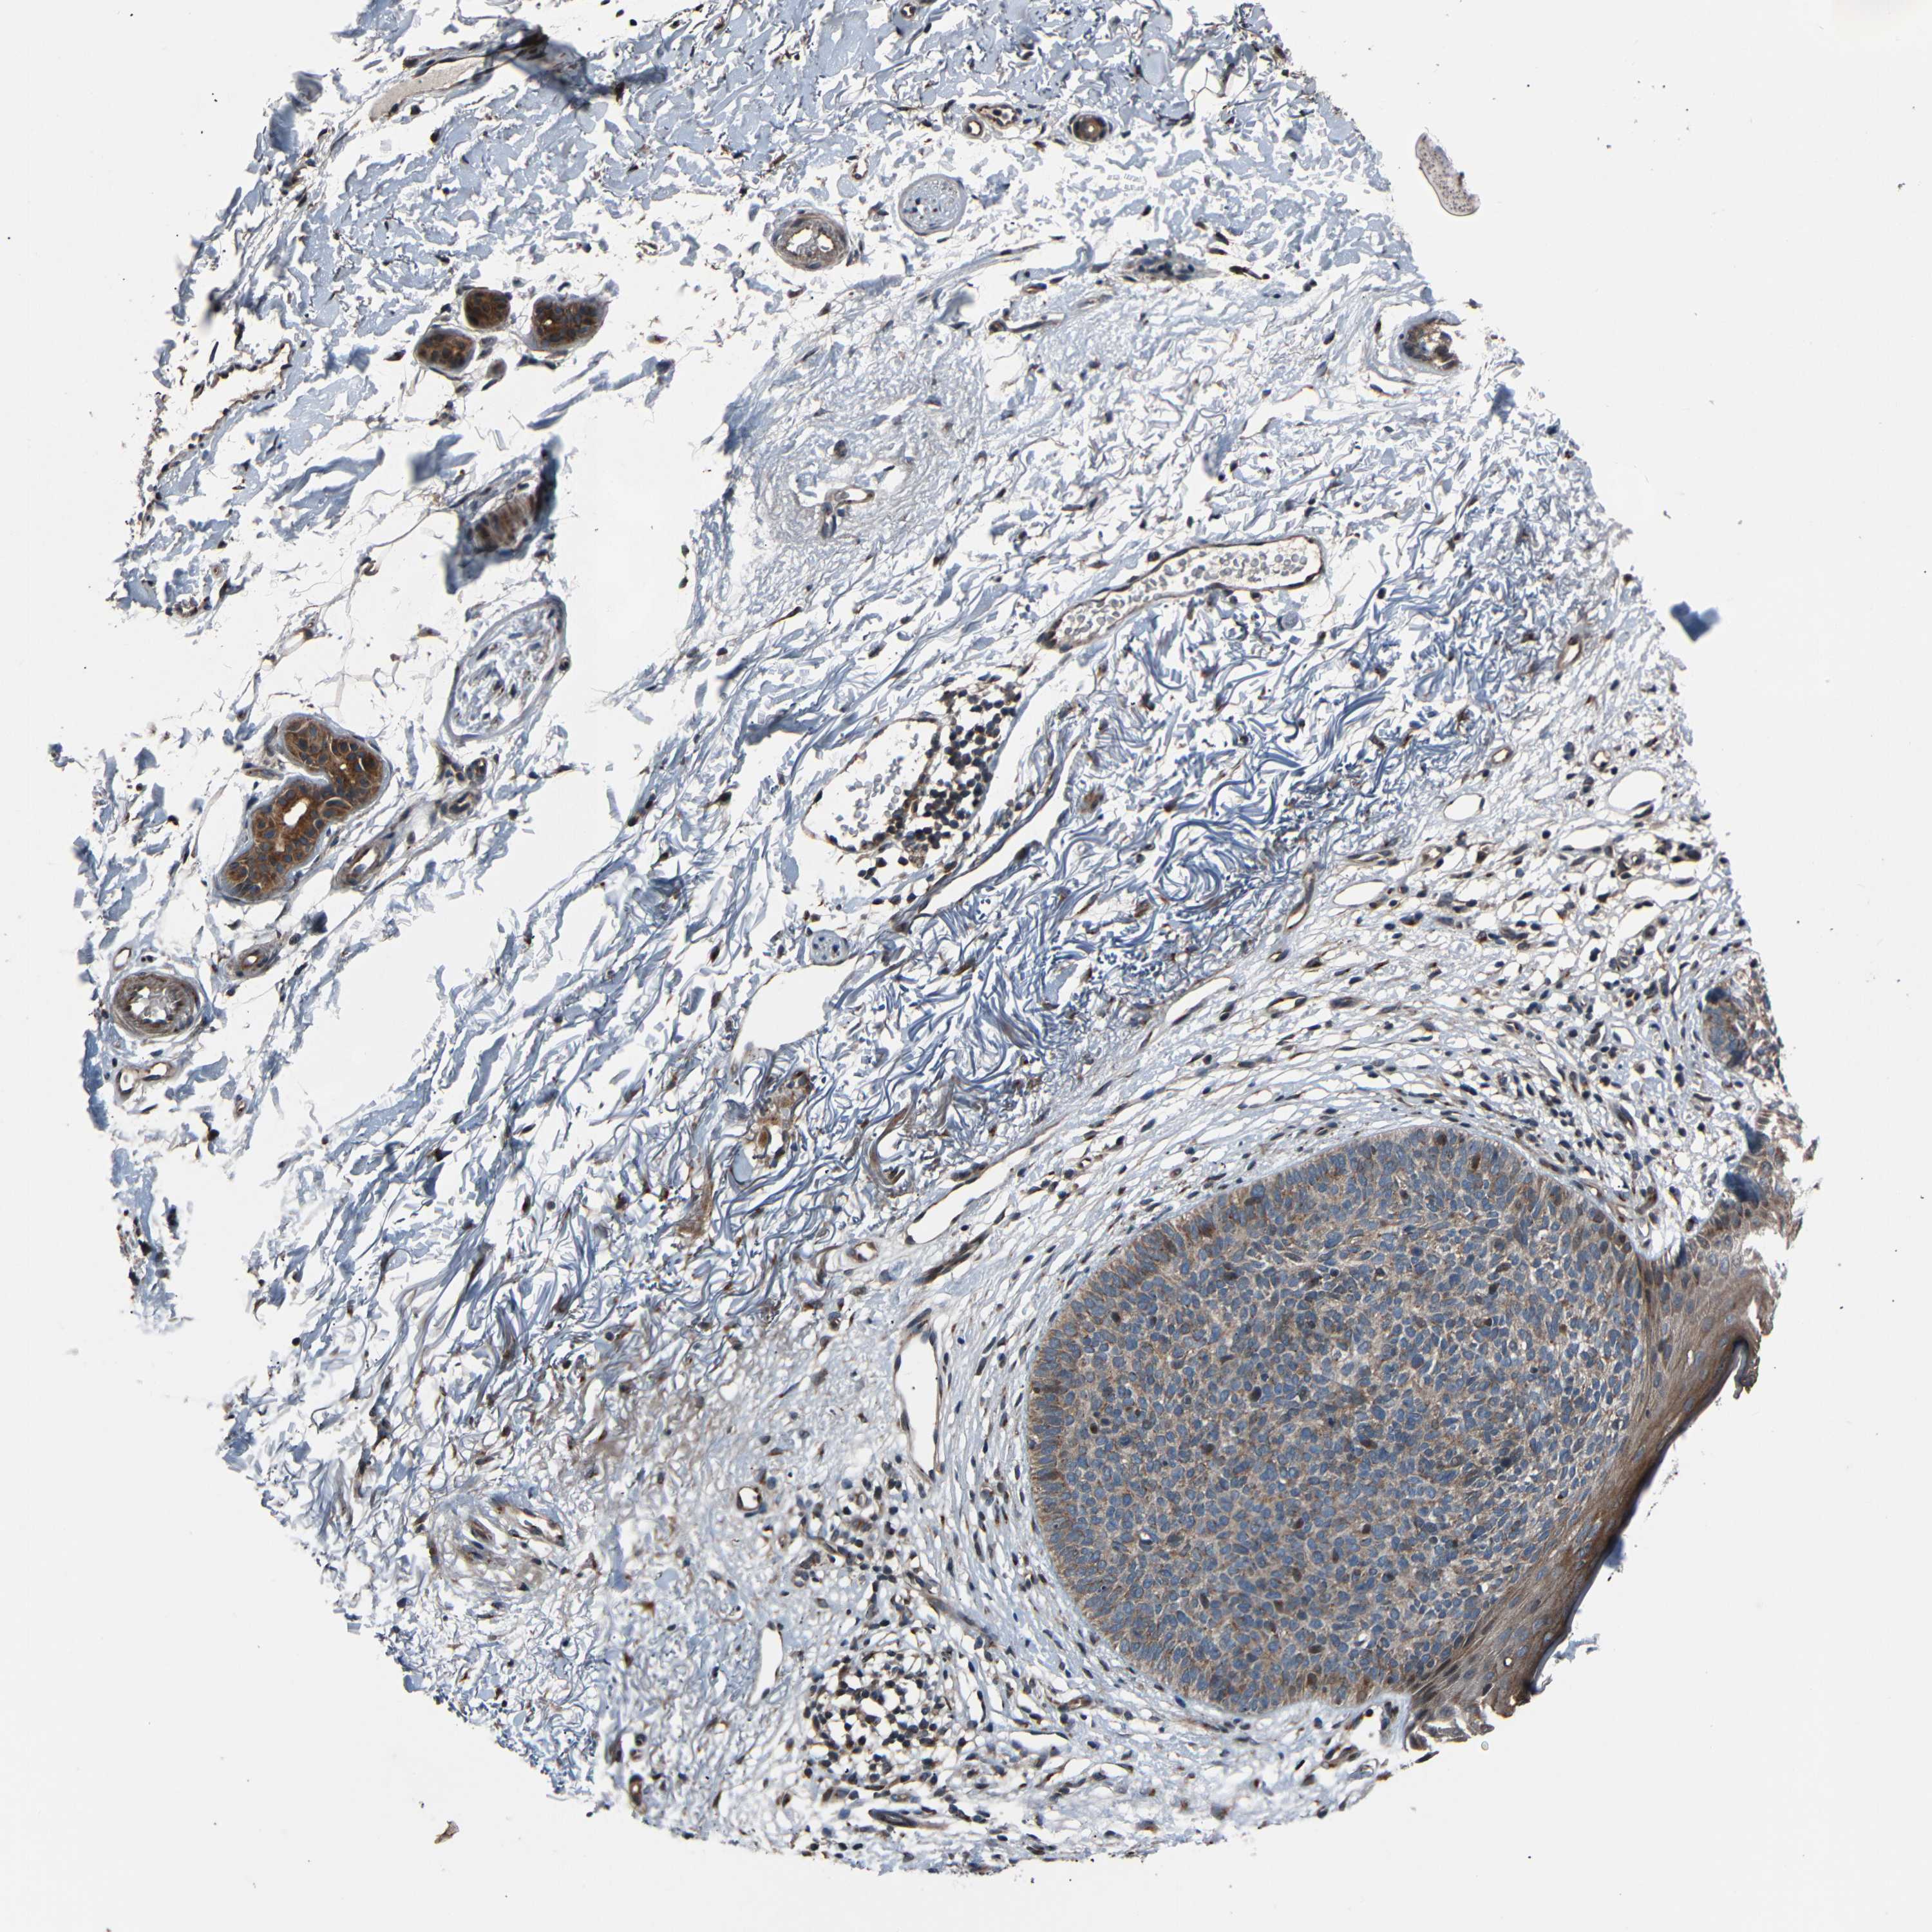

SKIN CANCER - Protein expressioni

A mouse-over function shows sample information and annotation data. Click on an image to view it in a full screen mode. Samples can be filtered based on level of antibody staining by selecting one or several of the following categories: high, medium, low and not detected. The assay and annotation is described here.

Antibody stainingi

Antibody staining in the annotated cell types in the current human tissue is reported as not detected, low, medium, or high, based on conventional immunohistochemistry profiling in selected tissues. This score is based on the combination of the staining intensity and fraction of stained cells.

Each image is clickable and will lead to virtual microscopy that enables deeper exploration of all samples and also displays staining intensity scores, fraction scores and subcellular localization as well as patient and tissue information for each sample.

Antibody HPA026109

Staining

High

Medium

Low

Not detected

Intensity

Strong

Moderate

Weak

Negative

Quantity

>75%

75%-25%

<25%

None

Location

Nuclear

Cytoplasmic/membranous

Cytoplasmic/membranous,nuclear

Basal cell carcinoma